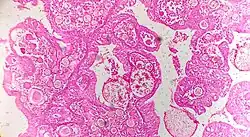

Serous cystadenoma | Histopathology of serous cystadenoma, with admixed scattered ciliated cells. This case closely resembles normal surface endometrial epithelium of the uterus | Category: Histopathology of ovarian serous cystadenoma | Ovarian cystadenoma |

![]() |